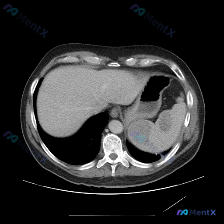

看到一份上腹部CT的影像资料,发现了一个很典型的偶发性脾脏小病灶,整理一下完整的分析思路,大家可以一起讨论。 --- 先看影像发现 这是一份上腹部CT平扫横断面图像,核心发现很明确: - 肝脏、胃、腹膜后等其他结构:在这个层面上都没看到明显异常,没有积液,没有肿大淋巴结,腹主动脉这些大血管也很干净。...